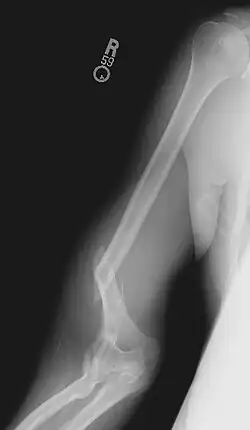

Типичная травма рукоборца.

Кажущаяся простота движений создаёт у многих иллюзию доступности вида спорта. Вид спорта травмоопасен: нагрузки на локтевые и плечевые суставы, связки, кости предплечья и плеча очень велики. Для избежания подобных травм, принципиально употребление кальция для укрепления базы (костей), практика (искусственный оппонент на основе тренажёров) и общее укрепление, упираясь на укрепление жил/сухожилий для предотвращения разрывов мышц.